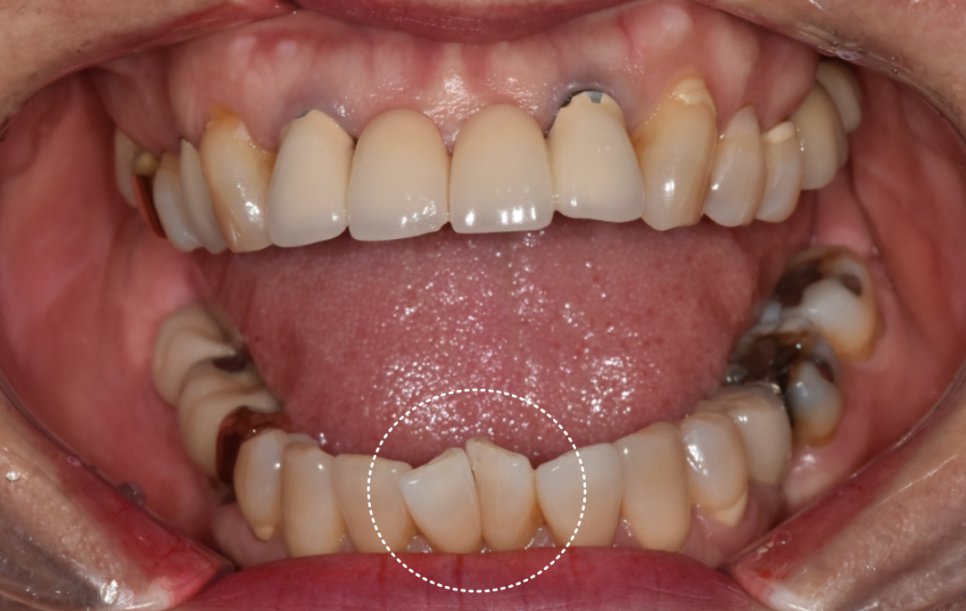

이번 환자분의 경우를 살펴보겠습니다.

10년 전 앞니 4개 브릿지를 하셨는데,

흔들림이 느껴져 내원하셨습니다.

기존 브릿지를 살펴보니 도자기 재질이었는데

군데군데 깨져 있습니다.

240622

또 양쪽 끝 치아 2개에 포스트(기둥)가 박혀 있었습니다.

포스트를 했다는 것은 치아머리 부분이 많이 없었다는 뜻입니다.

즉, 치아가 약한 상태였던 거죠.

환자분께 솔직하게 말씀드렸습니다.

브릿지를 떼어보면 이 기둥 박은 치아들은

아마 못 살릴 수도 있다고요.

그렇게 되면 양쪽 송곳니까지 포함해서

6개로 브릿지를 만들어야 한다고 설명드렸어요.

게다가 앞니 2개는 이미 오래전에 뽑은 상태라

뼈가 많이 흡수돼 있었습니다.

임플란트를 심기에는 뼈가 너무 얇았죠.

환자분과 충분한 상의 후 브릿지로 진행하기로 했습니다.